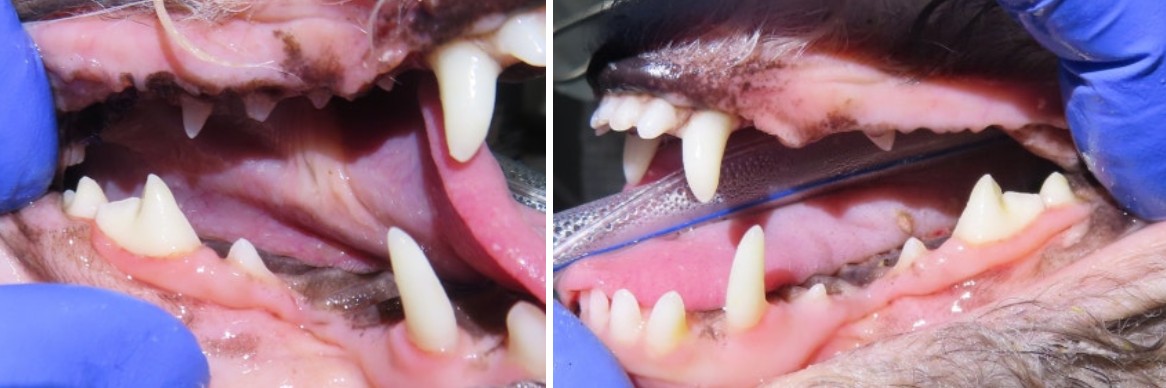

최근 서울 강북구 쌍문동 동물병원 비아츠에는 입가 염증이 반복되는 말티푸 아이가 내원했고, 정밀 방사선 촬영 결과 양측 상악 제1대구치(M1)에서 치내치가 확인되었습니다.

겉으로 보면 단순한 깊은 홈처럼 보일 수 있습니다.

구각염 반복

음식 섭취 시 불편

특정 부위 저작 회피 단순 치주염으로 보기에는 반복 양상이 이상했습니다.

강북구 동물병원 비아츠에서는 치과 질환이 의심될 경우 단순 육안 검사에 그치지 않습니다.

✔ 전신 마취 하 구강 정밀 검사